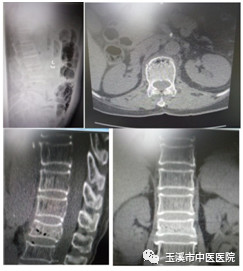

術(shù)前影像資料